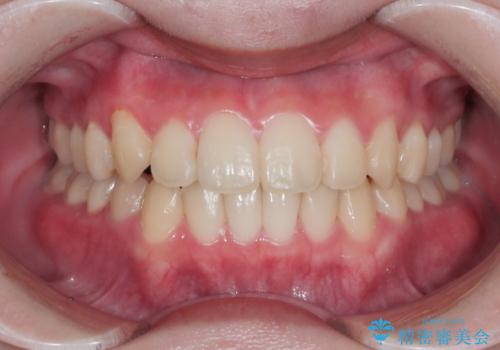

八重歯とクロスバイト:インビザライン治療